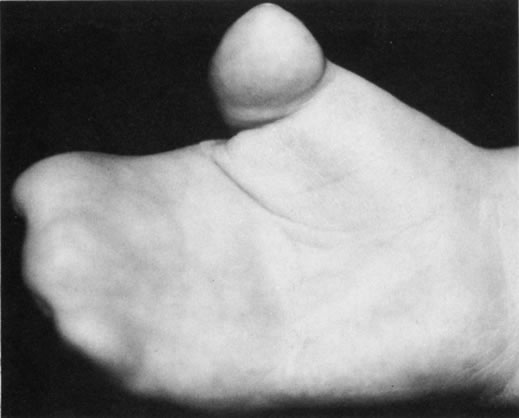

Many congenital cystic structures may arise from or involve the orbit. Some cystic structures, such as meningoencephaloceles or mucoceles, result from defects in the bony sutures of the cranial skeleton, allowing herniation of adjacent structures into the orbit. Other cystic structures, such as dermoid cysts, teratomas, and epithelial cysts, result from developmental anomalies of the orbital soft tissues. Most isolated orbital cysts have a subtle clinical presentation at birth, although some may present with extreme proptosis (Fig. 3). Ultrasonography can aid in the prenatal detection and monitoring of large orbital cysts.5